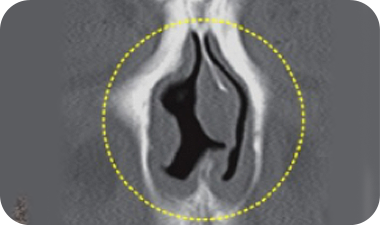

鼻中隔湾曲症

鼻中隔とは、鼻の中央に垂直に軸を成し、鼻の穴を分ける壁のことをいいます。

この鼻中隔が曲がったり、ねじれたりしている状態を鼻中隔湾曲症といいます。

鼻中隔が曲がった状態によって鼻中隔湾曲症C型とS型に分類することもあり、鼻づまり、鼻炎、

蓄膿症などの機能的な障害を引き起こします。

鼻中隔湾曲症の

手術ノウハウ

鼻中隔が曲がった状態に応じて、曲がった部分の鼻中隔軟骨を除去し、

残った鼻中隔軟骨を利用して鼻先の形や高さを正しく矯正します。

手術前 曲がった鼻中隔

手術後 まっすぐに矯正された鼻中隔